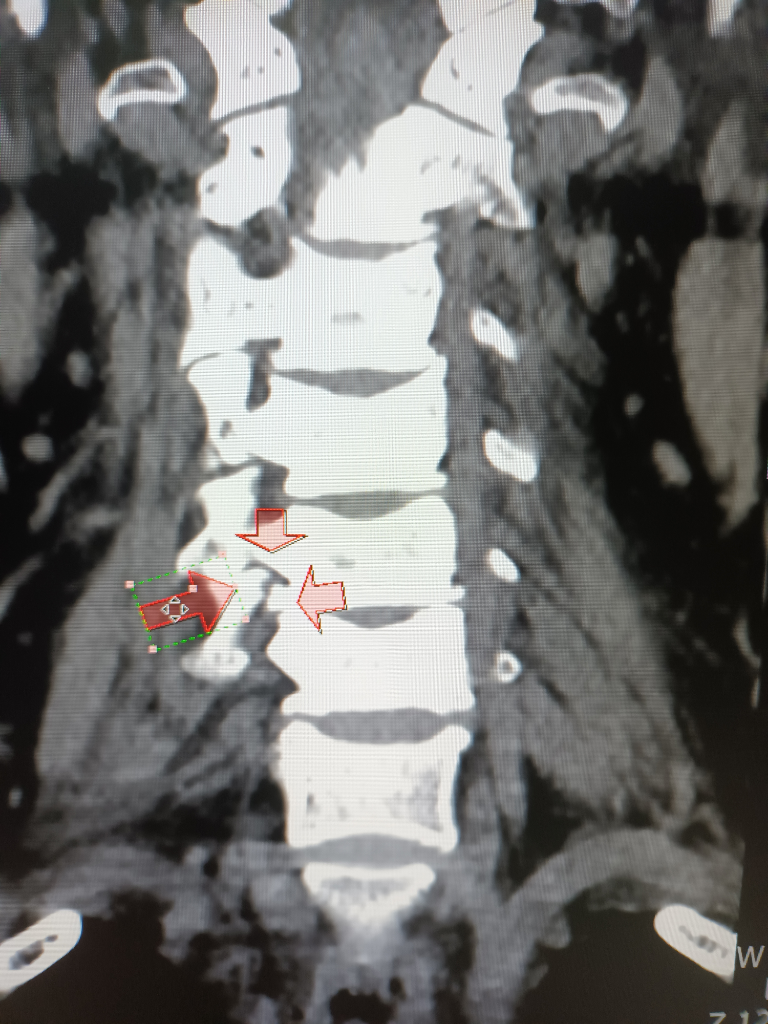

비보호 좌회전에서 파란불에 직진중 상대방차가 과속해서 사고가 났구요 119타고가서 병원에 입원했는데 목보호대만 하고 있는데 4일이 지나도 팔도 안올라가고 상태가 안좋아 mri찍었는데 갑자기 큰병원가서 정밀검사받으라고 그병원 앰블런스로 대학병원 응급실로 왔구요 바로 입원하고 수술하자고.경추6.7번골절 경추5번이 신경을 눌러서 팔이 안올라가는거라고 하네요 다음날 수술하고 잘됐다고 3개월은 지나야 좋아진다고 하는데 수술끝나고 퇴원하라고 하네요 수술한 당사자는 계속 등이랑 팔 가슴쪽 통증을 호소하네요 매일 진통제약이랑 주사 맞고 있는데 약기운 떨어지면 많이 아파해요 ~집가까운정형외과로 가야할거 같은데 아직 정확한 진단주수도 모르고 재활하고 언제쯤 합의해야 하는지 어느 정도 입원해야 하는지 후유장해진단도 받는건지 합의금은 어느정도인지 전혀 모르겠어요 자세한 말씀 부탁드려요

상해정도는 경추골절로 유합술을 시행한 상황으로 충분한 재활 치료를 한후 그에 따른 후유장해진단을 받아야 합니다.